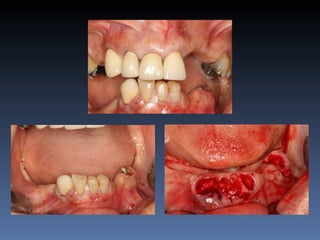

BOX 1

Maura Graça Montereiro

Idade – 59 anos

Sexo – Feminino

Raça – Caucasiana

ASA – II

Data- 27-04-2012

Diagnóstico: Desdentada total maxila

já reabilitada com “All-on-four” híbrido;

periimplantite dos implantes anteriores.

Plano de tratamento:         Remoção dos implantes

anteriores, instalação de dois implantes Zigomáticos

e dois implantes posteriores na tuberosidade.